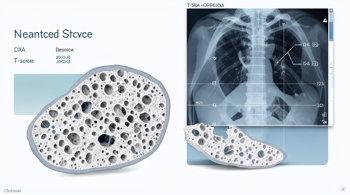

Read MoreOsteoporosis early detection has moved well beyond the traditional DXA scan, with artificial intelligence now repurposing routine chest...